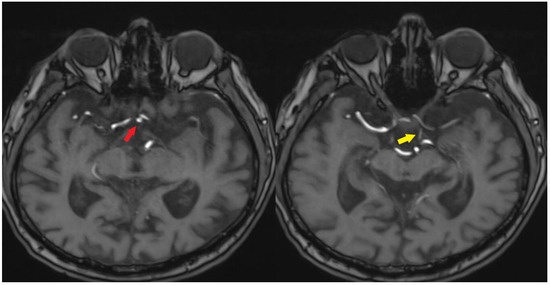

A review of the patient’s radiologic records revealed a cranial CT angiography performed nine years ago. Imaging showed no contrast in the left internal carotid artery. In addition, the left petrosal carotid canal was found to be intact (Figure 5 and Figure 6).

Figure 5.

CTA image obtained from the patient nine years ago [White arrow: indicates a filling defect beginning at the proximal segment of the ICA].